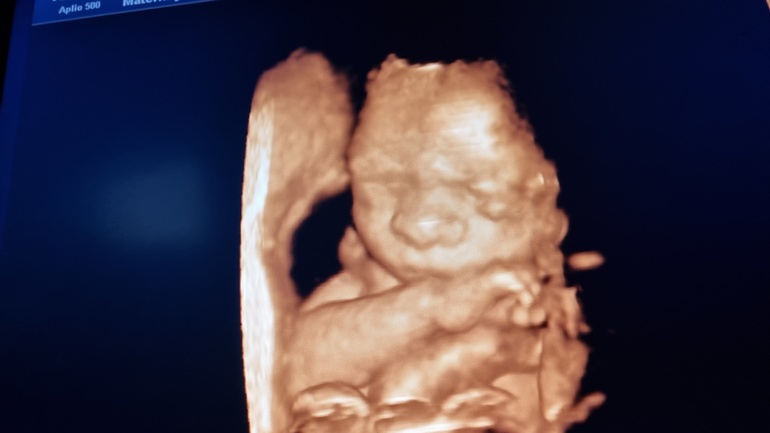

Сходила на 3д узи и обалдела от технологий 😍 абсолютно всё! видно - щёчки, губки,особенно носик папин 😄 как он загордился от этой новости, надо было видеть. Кстати если в жк хорошая узистка, рекомендую делать через них платно, намного дешевле, чем в частных.

3д - это нечто, да. )) Тоже пару дней назад была, сделали фото, такая милота. Вылитый я, кроме носа, только подбородок папин. Чей нос - пока непонятно, будем выяснять после рождения. )

Мне на 20ой неделе сделали 3д УЗИ и так четко, так хорошо мою красотку было видно 😁 повесили на холодильник каждый день любуюсь)